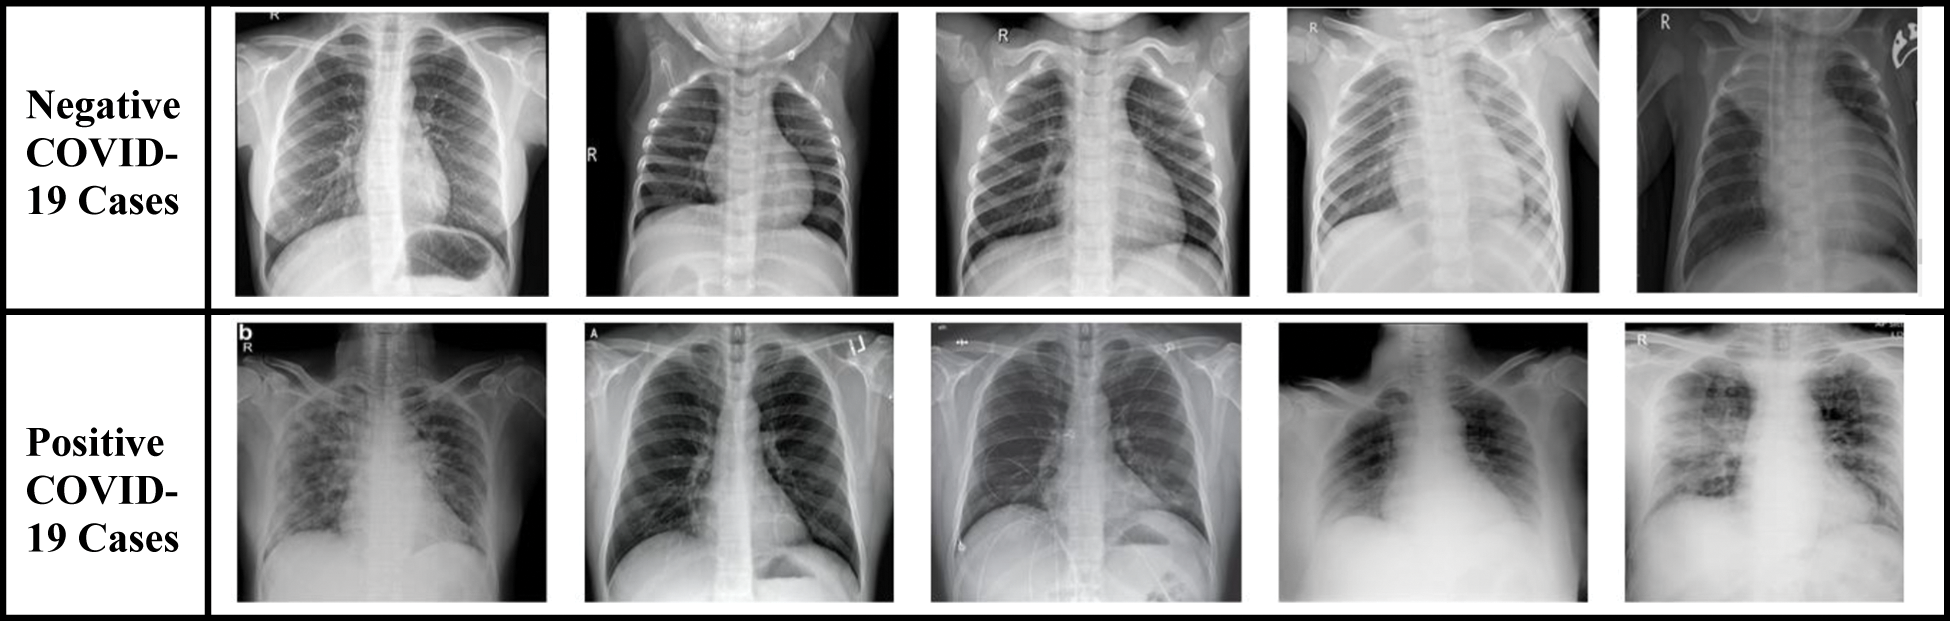

To evaluate the performance of the proposed technique, two different datasets are used: dataset-1 [57, 58] and dataset-2 [59, 60]. These datasets include X-ray images that are divided into two classes: (i) negative COVID-19 cases, and (ii) positive COVID-19 cases. Fig. 15 presents a sample of both classes extracted from the datasets. However, X-ray images with positive COVID-19 cases have a pattern of ground-glass opacification along with other indicators such as consolidation in the patchy areas and having a bilateral area [61].

Figure 15: Sample of original chest X-ray dataset